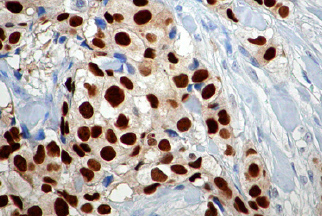

Exames Imunohistoquímicos

Painel Imunohistoquímico para câncer de mama

Hibridização "in situ"